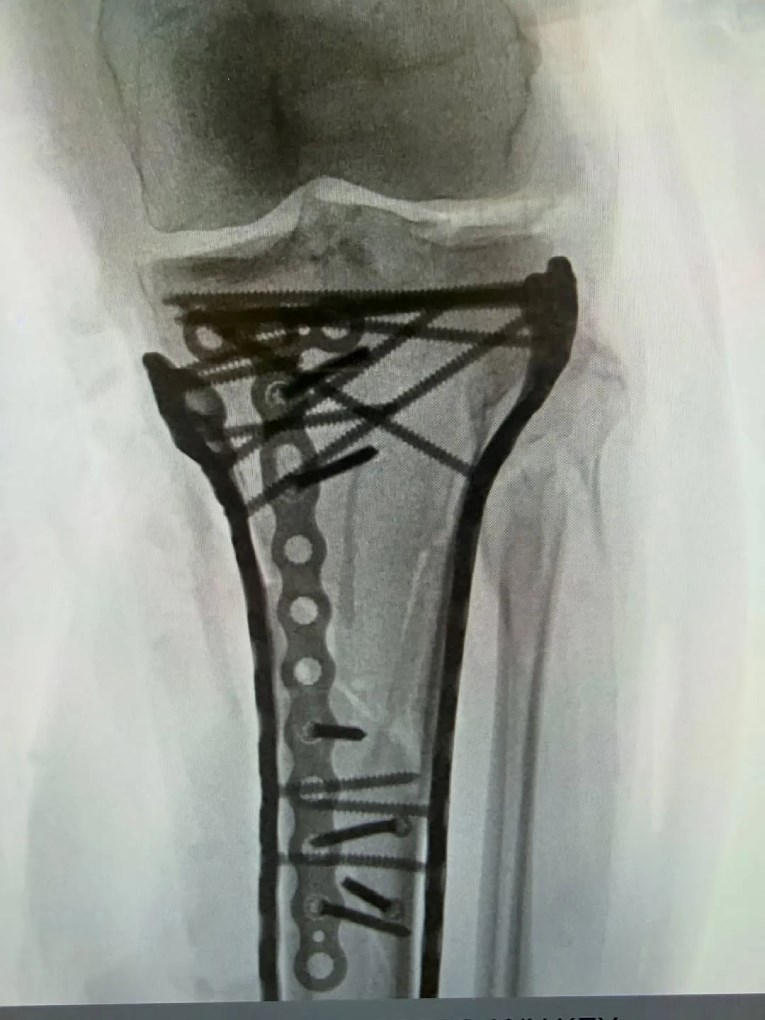

– Preživela sam operaciju… Trajala je nešto više od šest sati. Kao što vidite, trebalo je puno pločica i šrafova da se sve spoji, ali doktor Heket je napravio neverovatan posao. S obzirom na težinu povrede, oporavak nakon operacije ide malo teže i još nisam otpuštena iz bolnice. Ali blizu sam. Korak po korak. Uskoro ću detaljnije objasniti o kakvoj se povredi radi i šta sve to znači – napisala je Lindzi Von.

Ona je uz objavu priložila i dve rendgenske fotografije koje jasno prikazuju veliki broj metalnih pločica i šrafova ugrađenih u njenu nogu. Sve je to bilo potrebno kako bi se kost stabilizovala i omogućio proces zarastanja.